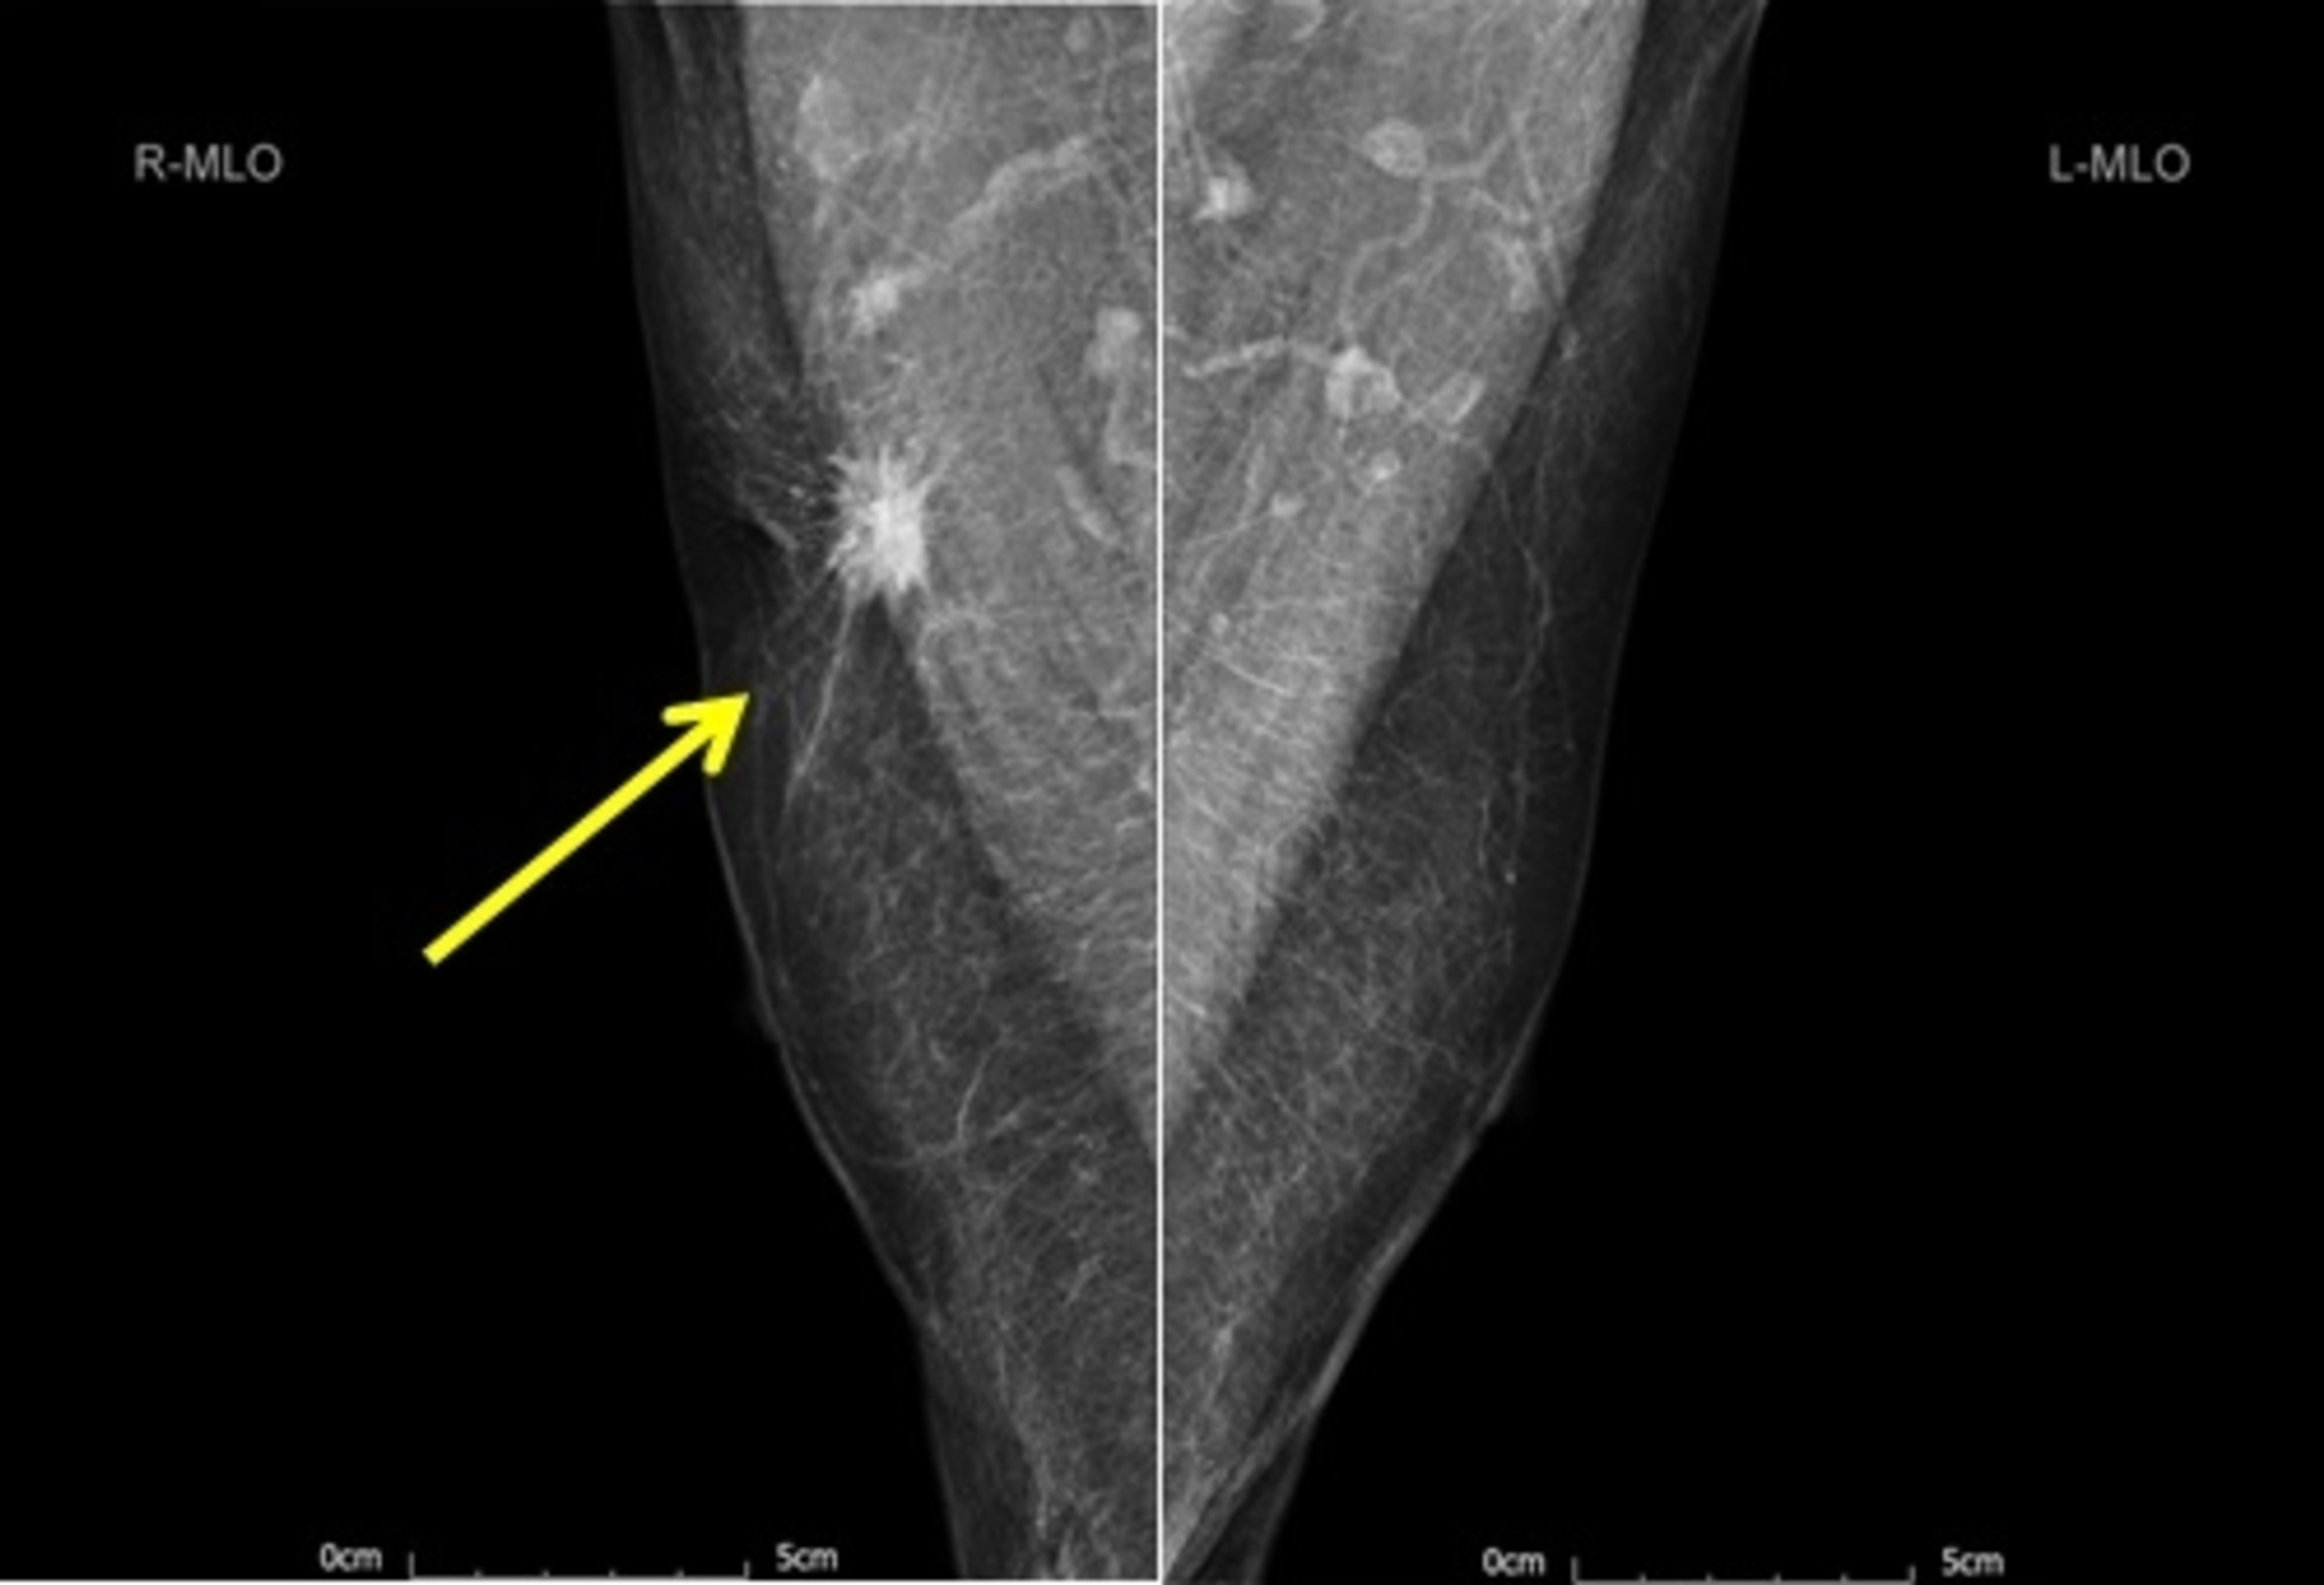

Mammogram (Figure 1) showed a 25-mm suspicious lesion in the right axillary tail, which was also visualized on ultrasound (Figure 2), along with a suspicious lymph node in the right axilla. Imaging-guided core biopsies were taken from both; the histopathology was consistent with grade 1 invasive ductal carcinoma, and ER 0, PR 0, and HER 2 negative as well. Mastectomy with axillary clearance was performed after consultation with breast MDT (multidisciplinary team). The post-operative histopathology revealed 23-mm, grade I, triple-negative invasive ductal carcinoma (Figure 3) with lymphovascular invasion, Ki67 10%, one out of nine lymph nodes showing metastatic disease, and the final staging as T2N1M0. The MDT advised for annual surveillance for five years.